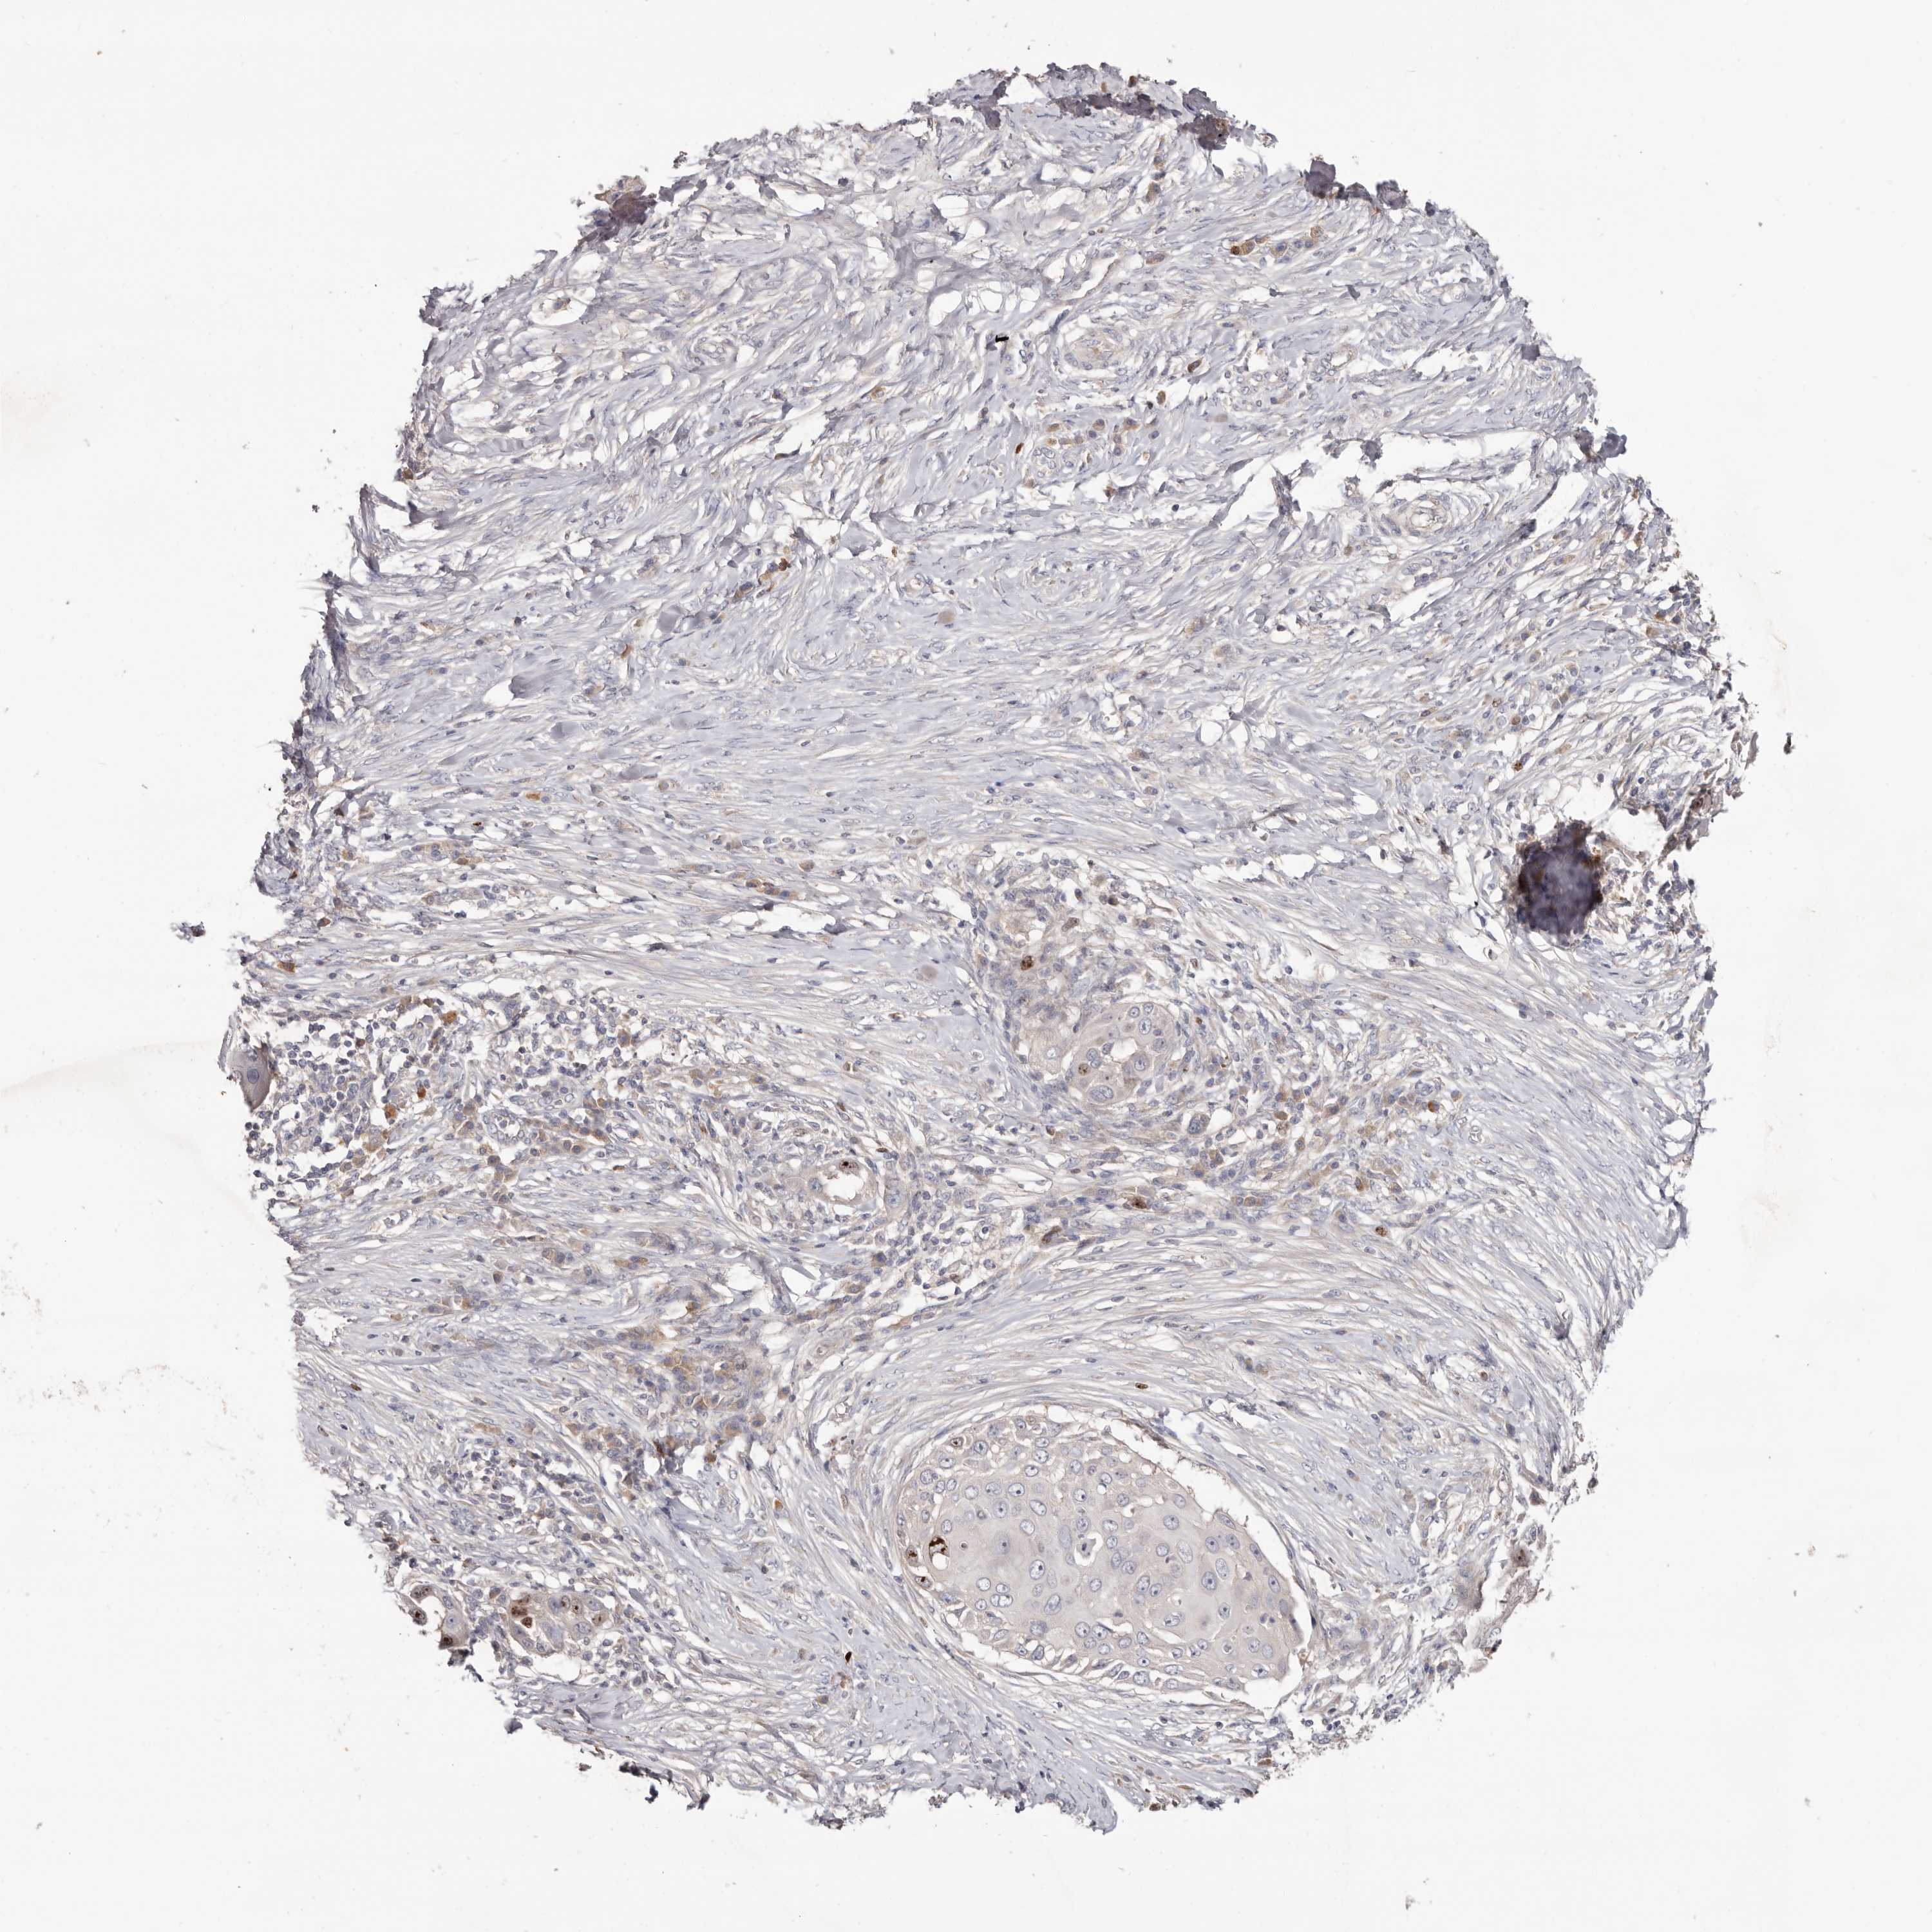

SKIN CANCER - Protein expressioni

A mouse-over function shows sample information and annotation data. Click on an image to view it in a full screen mode. Samples can be filtered based on level of antibody staining by selecting one or several of the following categories: high, medium, low and not detected. The assay and annotation is described here.

Each image is clickable and will lead to virtual microscopy that enables deeper exploration of all samples and also displays staining intensity scores, fraction scores and subcellular localization as well as patient and tissue information for each sample.

Antibody HPA028579

Basal cell carcinoma